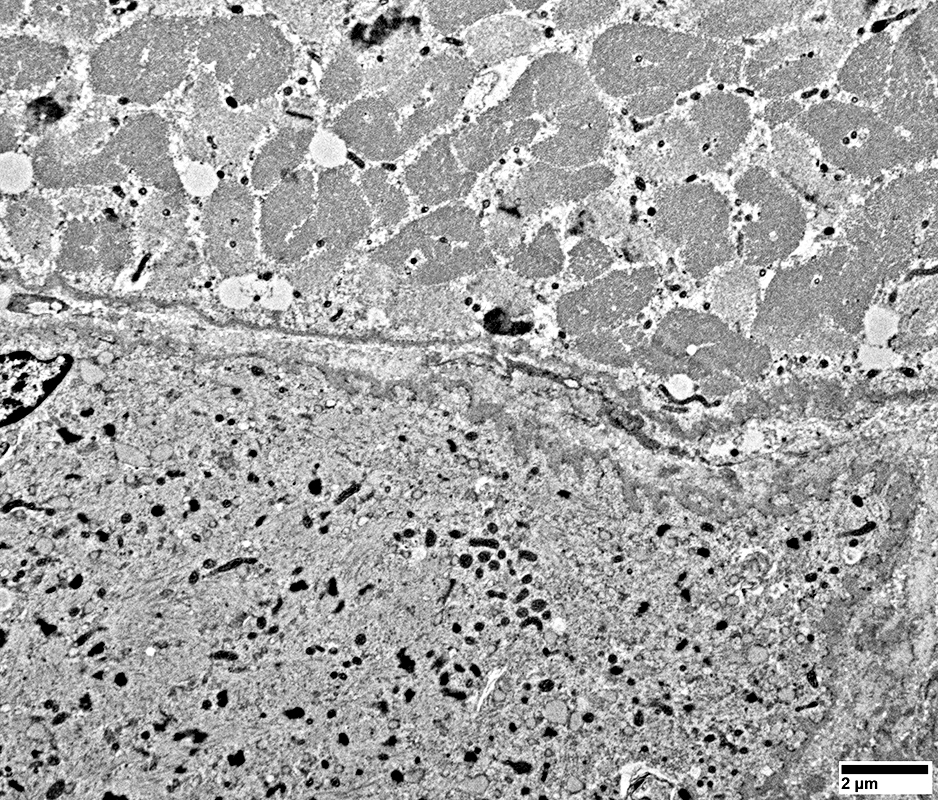

Perifascicular atrophy: Toluidine blue-stained plastic sections

Muscle fibers: Atrophic in perifascicular regions; Irregular sarcolemmal membrane

Muscle fibers

Size: Atrophic

Sarcolemmal membrane: Irregular

Contain lipid droplets

DM-VP Muscle Fibers: Sarcoplasm Ultrastructural Morphology

DM-VP Muscle Fibers: Varied degrees of damage

Fibers at top left & right have marked sarcomere disorganization

Muscle Fiber at bottom of images has

Sarcomeres: Marked disorganization

Mitochondria: Proliferation; Coarse cristae; Often small size

Basal lamina: Thick undulating (Compare to normal muscle fiber above)

Cytoplasmnic vacuoles: Possibly derived from Endoplasmic Reticulum

From: R Schmidt